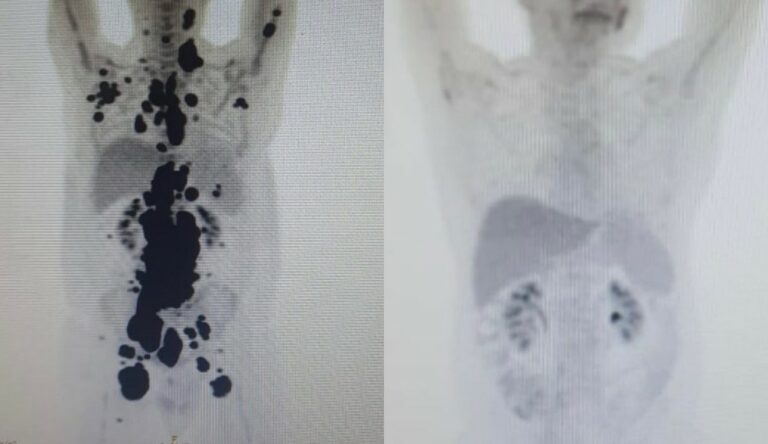

“Foi uma resposta muito rápida e com tanto tumor. Fico até emocionado [ao ver as duas ressonâncias de Paulo]. Fiquei muito surpreso de ver a resposta, porque a gente tem que esperar pelo menos um mês depois da infusão da célula. Quando a gente viu, todo mundo vibrou. Coloquei no grupo de professores titulares da USP e todo mundo impressionado de ver a resposta que ele teve”, comemorou o especialista.

As duas imagens do Pet Scan (tomografia feita com um contraste especial ) (veja acima) representam “dois Paulos”: a da esquerda, o paciente que tinha como caminho único os cuidados paliativos, quando a alternativa é dar conforto, mas já sem expectativa de cura, e a da direita, um paciente com um organismo já sem tumores após o tratamento com CAR-T Cell.

“A vitória não é só minha. É da fé, da ciência e da energia positiva das pessoas. Cada uma delas ajudou a colocar um paralelepípedo nesse caminho. A imagem prova com muita clareza para qualquer pessoa a gravidade do meu linfoma, e eu não tinha ideia de que era assim”, contou o paciente.